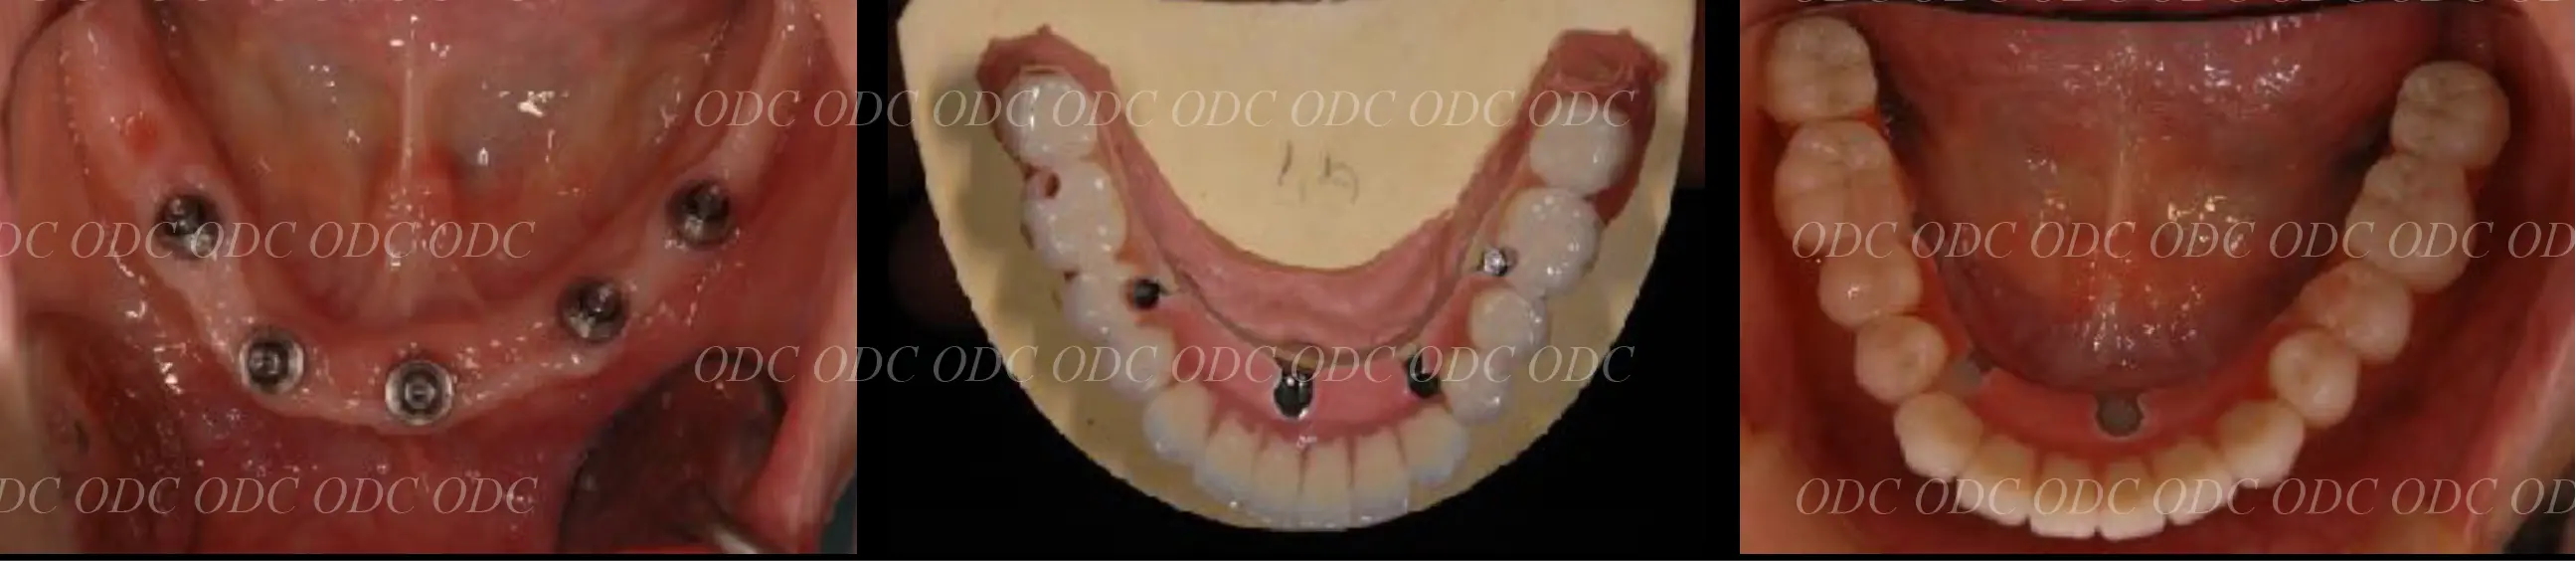

インプラントオーバーデンチャー症例

インプラントオーバーデンチャーとは、インプラントで入れ歯を支える方法です。

清掃がしやすいなどのメリットがあります。

また、多くの入れ歯の方が気持ち悪いと言われる上顎の内側の部分を大きく開けることができます。

上顎はCADCAMで作製されたバーを使用し、ロケーターとクリップを併用しています。

下顎は、ロケーターと呼ばれるアタッチメントで入れ歯が安定するようにしています。

インプラントオーバーデンチャーは、できれば3本以上のインプラントを使用すると安定しやすくなります。